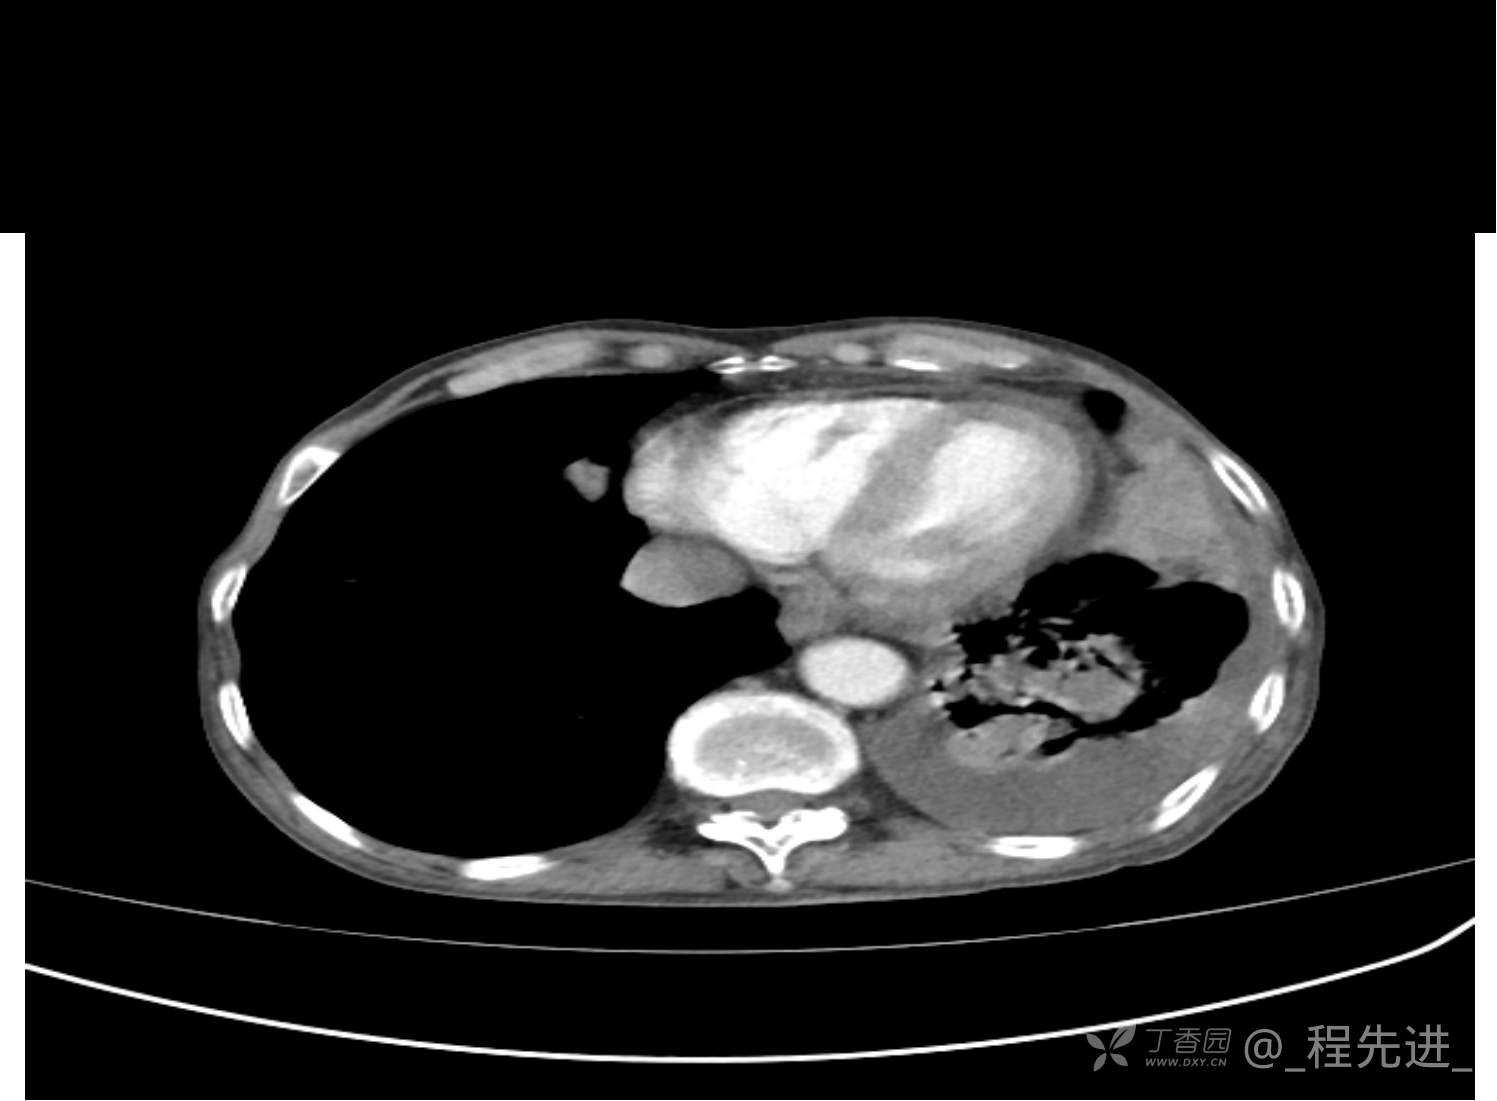

患者性别:男

患者年龄:81岁

简要病史:反复咳嗽、咳痰20余年,加重1周。两肺呼吸音低,可闻及散在干湿啰音。